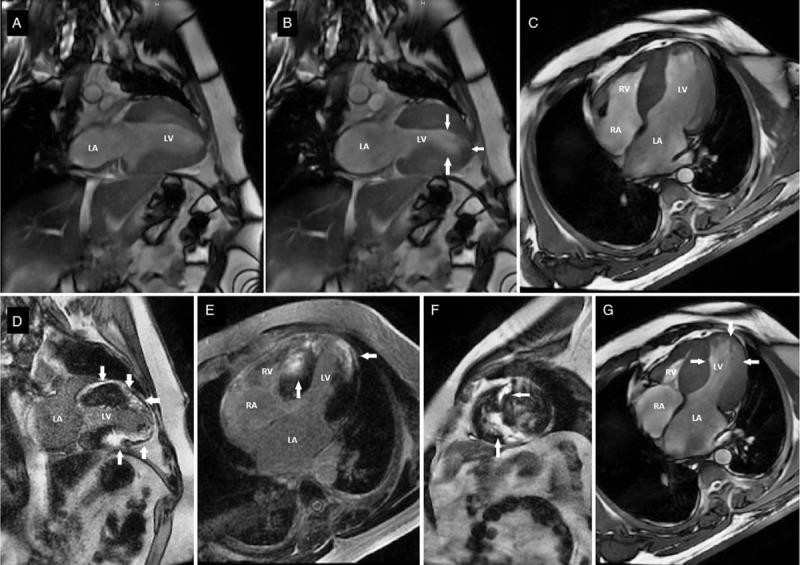

A 33-year-old man who presented with chest discomfort for 10 days. He had an emerging apical aneurysm in the LV without midventricular obstruction. He had been diagnosed with apical HCM via abnormal electrocardiograms (ECG) and single-photon emission computed tomography (SPECT) for 10 years. This time, a new significant change in ECG and SPECT was identified. Late gadolinium enhancement (LGE) was observed by cardiac magnetic resonance imaging (MRI), and SPECT showed myocardial fibrosis or necrosis involving the apical aneurysm and proximal portion of the heart, which was confirmed by left ventriculography.

一名33岁男性,因胸部不适10天前来就诊。他左心室出现了一个新的心尖部动脉瘤,无室中隔梗阻。他通过异常心电图(ECG)和单光子发射计算机断层扫描(SPECT)被诊断为心尖部HCM已有10年。此次,ECG和SPECT出现了新的显著变化。心脏磁共振成像(MRI)观察到晚期钆增强(LGE),SPECT显示心肌纤维化或坏死累及心尖部动脉瘤及心脏近端部分,左心室造影证实了这一点。